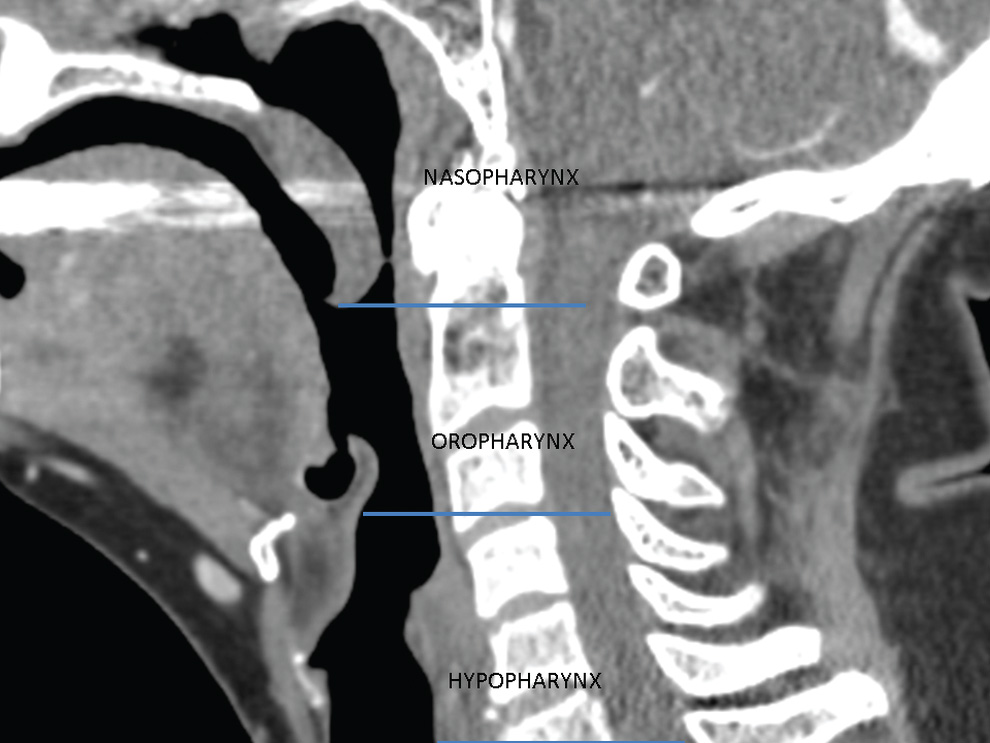

Oropharyngeal Anatomy Radiology . Describe abnormalities detected at fluoroscopic swallowing examination. Emphasis is placed on the. (a) anatomical divisions of the pharynx and their boundaries. Familiarization of the normal appearance of the oral cavity and oropharynx on mri is critical to recognize and describe these types of pathology. The oropharynx forms part of the pharynx, being the continuation of the oral cavity and nasopharynx superiorly, and the larynx and. This article reviews the oral cavity. It communicates with the nasopharynx superiorly and the laryngopharynx inferiorly. (1) the oral mucosal surface, including. This article reviews the anatomy of the oropharynx and oral cavity, as seen on ct and mr imaging studies. Anatomy • the oropharynx is the posterior continuation of the oral cavity; The pharynx is composed of three parts: From an imaging standpoint, the oral cavity can be subdivided into four distinct regions: Posterior to the nasal choanae, extending from the vault. Discuss the anatomy and imaging phases of swallowing.

Oropharyngeal Anatomy Radiology Posterior to the nasal choanae, extending from the vault. It communicates with the nasopharynx superiorly and the laryngopharynx inferiorly. Familiarization of the normal appearance of the oral cavity and oropharynx on mri is critical to recognize and describe these types of pathology. This article reviews the oral cavity. Emphasis is placed on the. Anatomy • the oropharynx is the posterior continuation of the oral cavity; This article reviews the anatomy of the oropharynx and oral cavity, as seen on ct and mr imaging studies. The oropharynx forms part of the pharynx, being the continuation of the oral cavity and nasopharynx superiorly, and the larynx and. Discuss the anatomy and imaging phases of swallowing. (a) anatomical divisions of the pharynx and their boundaries. The pharynx is composed of three parts: Describe abnormalities detected at fluoroscopic swallowing examination. From an imaging standpoint, the oral cavity can be subdivided into four distinct regions: (1) the oral mucosal surface, including. Posterior to the nasal choanae, extending from the vault.